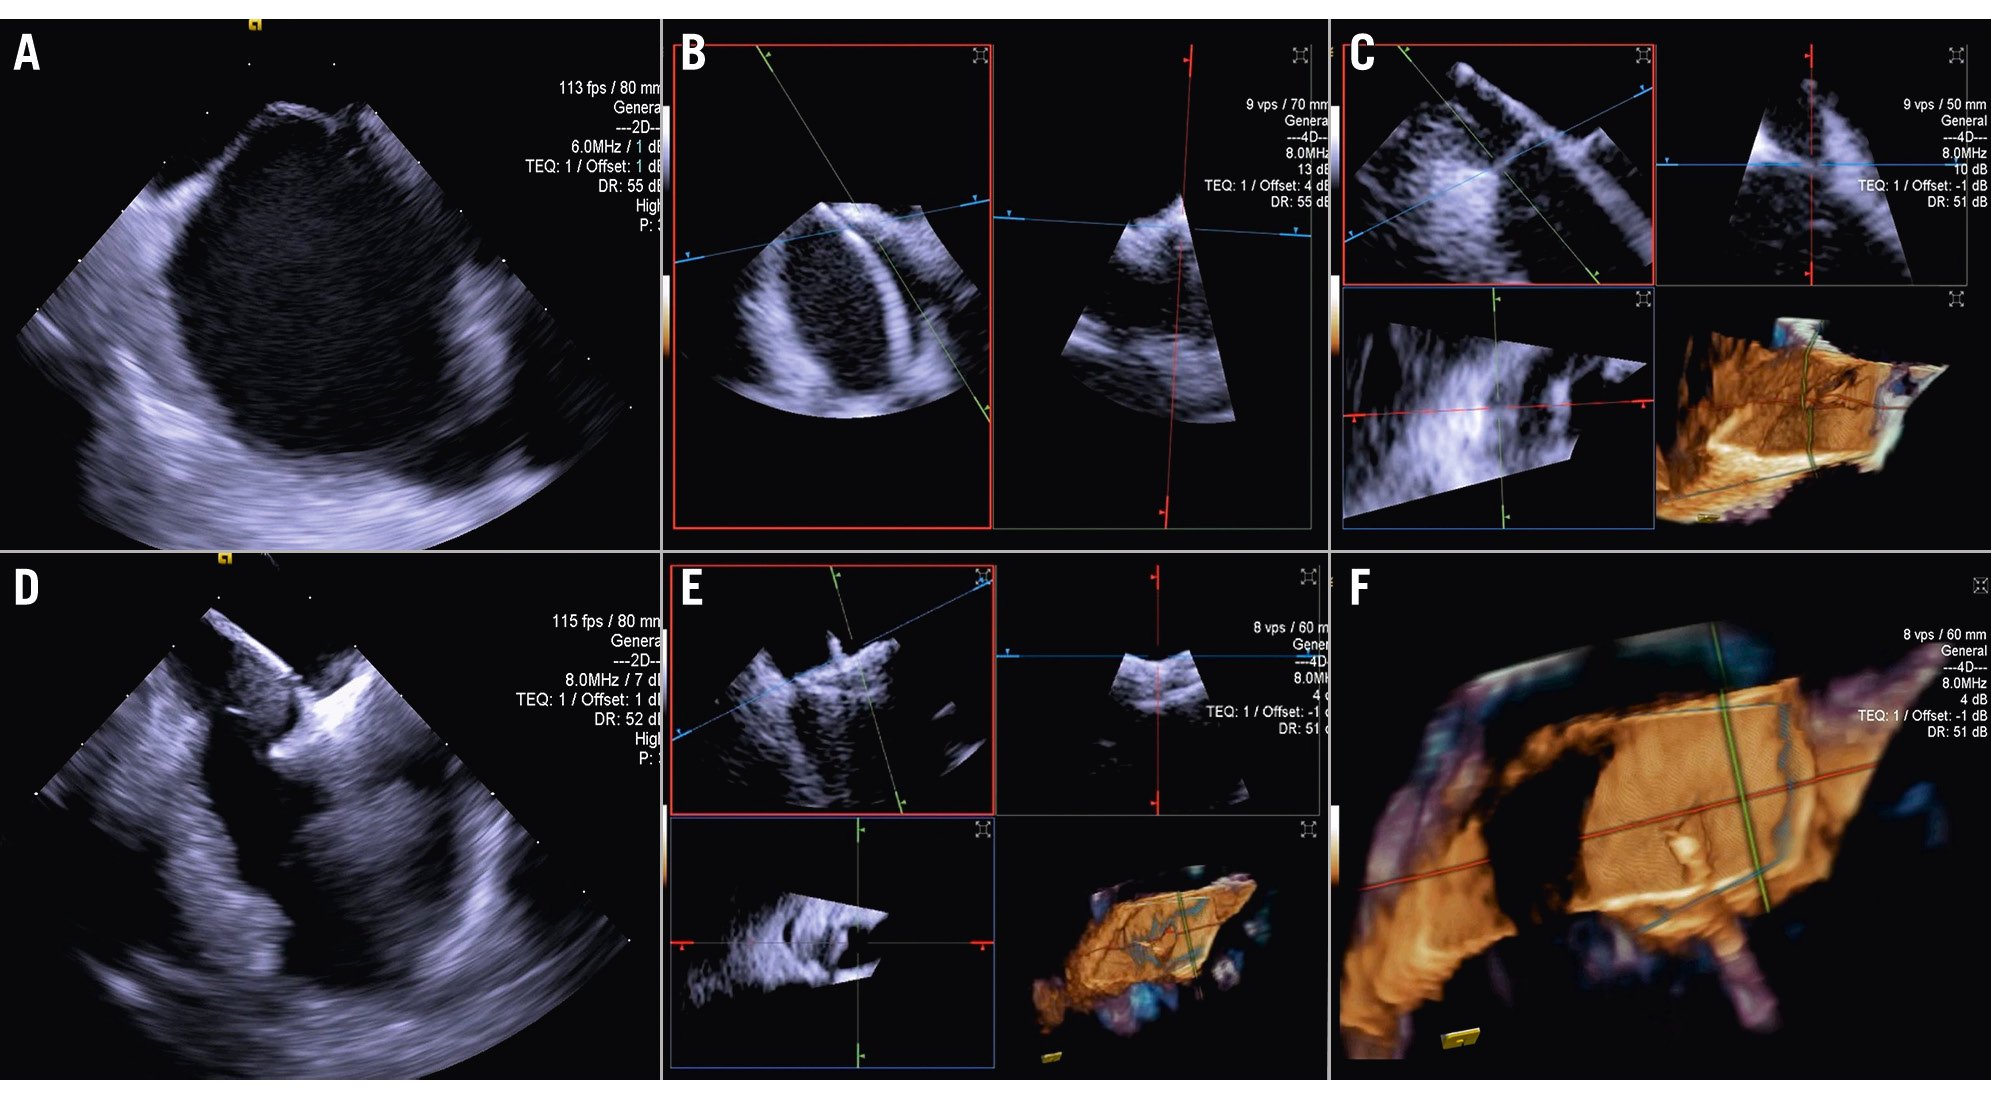

Central illustration. Current landscapes on 3D ICE utilisation. An overview of the key structural heart interventions that increasingly utilise 3D ICE: (A) mitral TEER/ViV; (B) IAS defect/ PFO closure; (C) Tricuspid TEER/TTVR; (D) LAAO. E) An illustration of the ICE probe’s position during imaging of the tricuspid valve. F) An illustration of the ICE probe’s position during imaging of the mitral valve. 3D: three-dimensional; ICE: intracardiac echocardiography; IAS: interatrial septum; LAAO: left atrial appendage occlusion; TEER: transcatheter edge-to-edge repair; TTVR: transcatheter tricuspid valve replacement; ViV: valve-in-valve